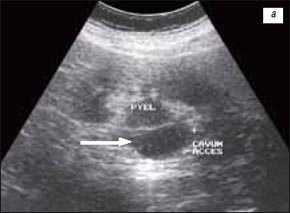

У 2 (1,2%) больных отмечена увеличенная "губа" над воротами почки (рис. 3а-в).

а) Эхограмма.

б) Экскреторная урограмма.

в) КТ с контрастным усилением.

Рис. 3 (г-е). Псевдоопухоль гипертрофия Бертена (неполная "перемычка" паренхимы) в среднем отделе правой почки.

г) Эхограмма.

д) Экскреторная урограмма.

е) КТ с контрастным усилением.